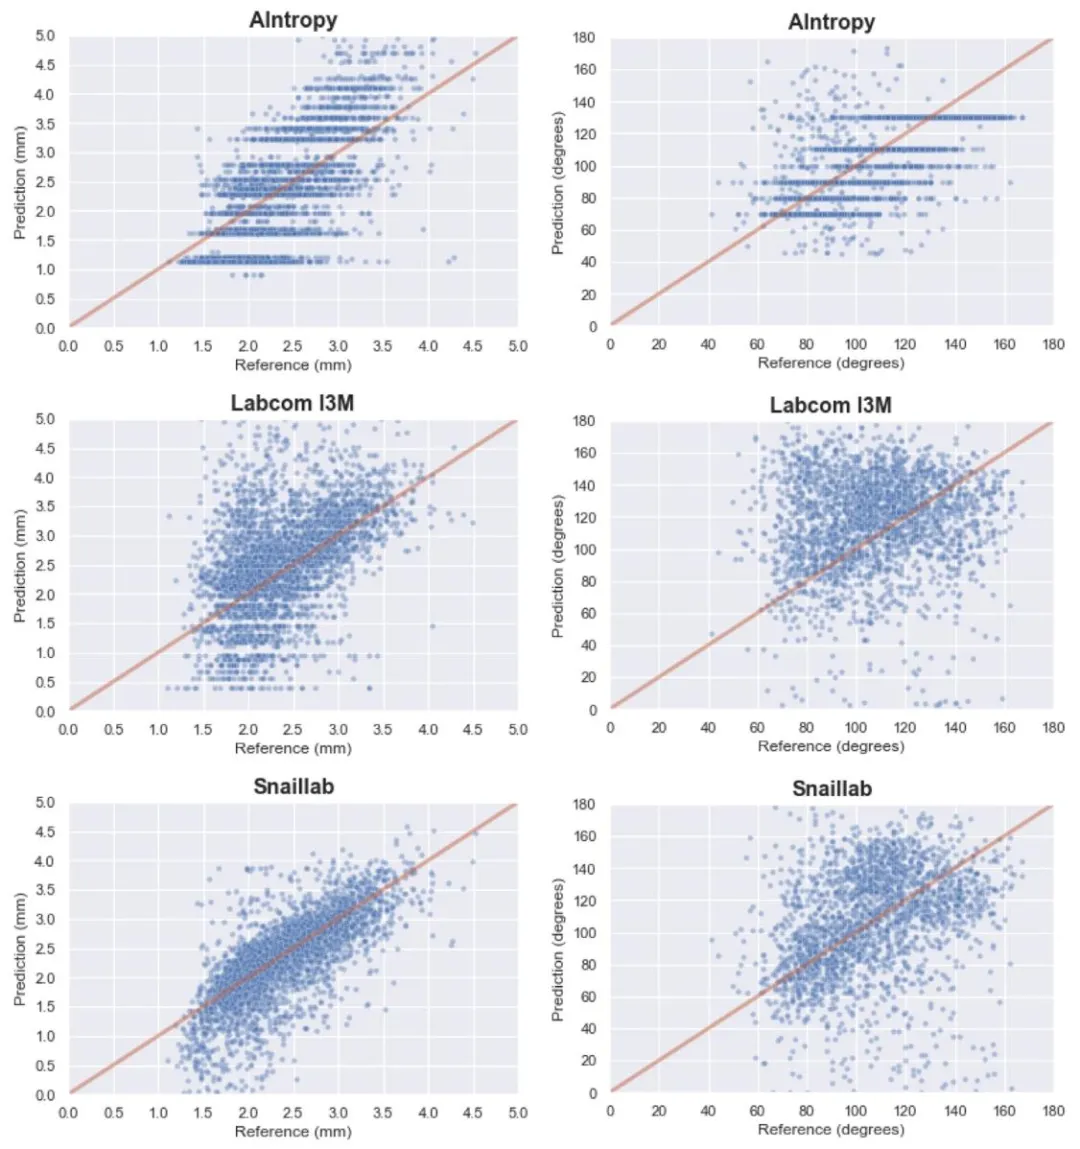

Fig. 8. Correlation between predicted and references values for each submitted solution to Task 2. The left column depicts plots per method for artery diameter predictions(x-axis) versus reference values (y-axis); the right column shows plots per method for bifurcation angle predictions (x-axis) versus reference values (y-axis). AIntropy consistentlypredicts distinct values that represent the mean for that specific artery or bifurcation. Both Labcom I3M and Snaillab teams’ methods predict diameters below 1.2 mm, indicatingunderestimations compared to the reference standard. Additionally, an overestimation of smaller bifurcation angles was observed for these two teams.

图 8. 任务 2 各提交方案的预测值与参考值之间的相关性左列展示了每种方法的动脉直径预测值(x 轴)与参考值(y 轴)的关系图;右列展示了每种方法的分叉角度预测值(x 轴)与参考值(y 轴)的关系图。AIntropy 团队的方法始终预测出特定动脉或分叉处的均值,呈现出明显的集中趋势。Labcom I3M 团队和Snaillab 团队的方法预测的直径均低于 1.2 毫米,与参考标准相比存在低估。此外,这两个团队的方法对较小的分叉角度存在高估现象。